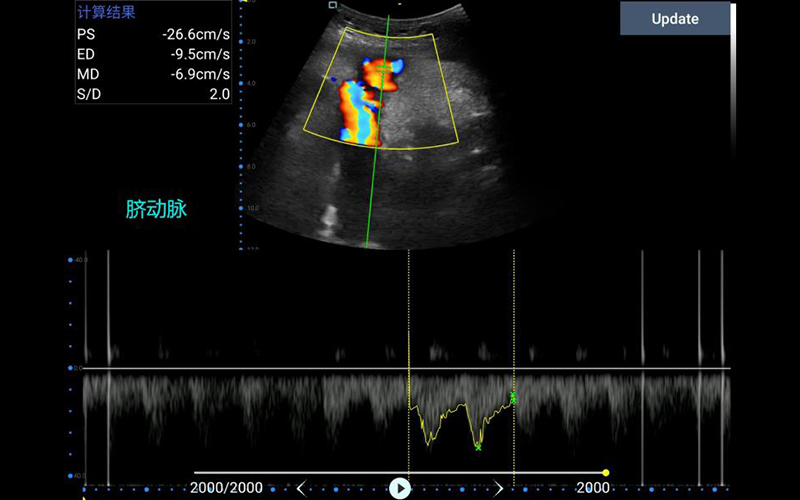

腹部

肾脏

妇科产科

心脏

肺等